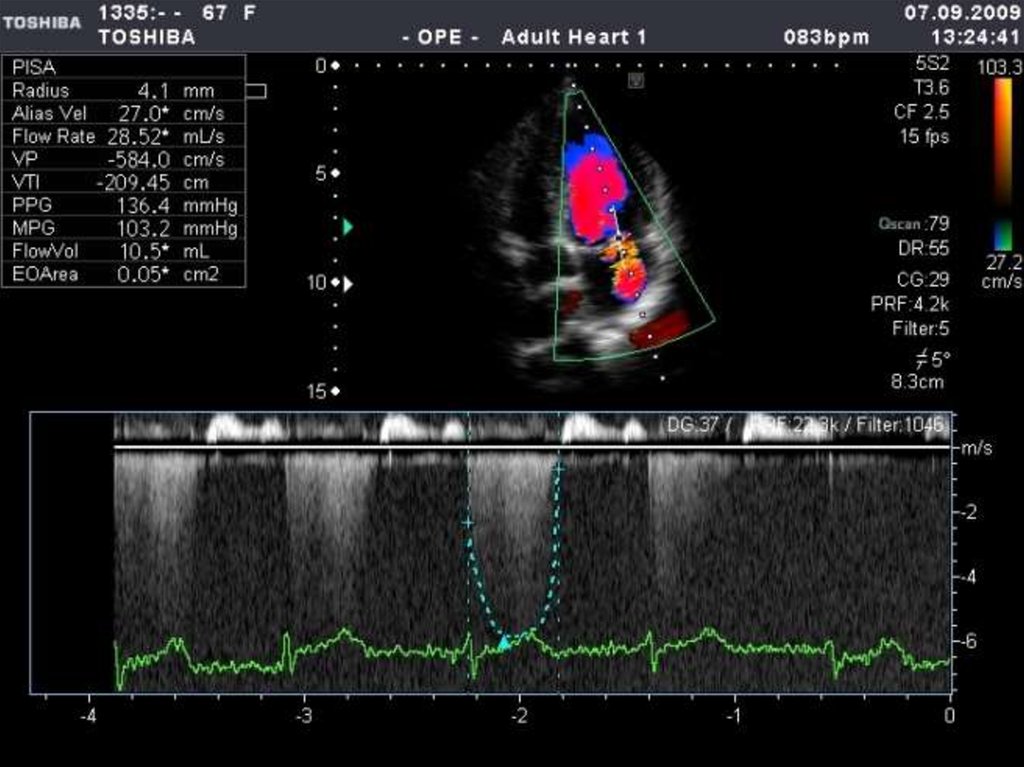

ЭХО-КГ: детализация порока, определение тактики

лечения